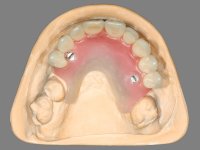

Inicialmente foram confecionadas duas novas próteses removíveis. O dente 1.3 foi extraído quando da colocação das próteses. Feito o estudo imagiológico necessário, foram colocados 4 implantes no maxilar superior. Após 3 meses de osteointegração foi feita a impressão para a confeção de ceras de articulação montadas em placa base aparafusadas aos implantes. Estas ceras foram utilizadas na recolha das relações inter-maxilares e na tentativa de proporcionar apoio ao lábio superior. Foi feita a prova de dentes com estes montados em placas base aparafusadas permitindo uma avaliação estética dinâmica muito interessante. Sendo validada esteticamente pela paciente, esta prova deu origem a uma muralha de silicone que orientou laboratorialmente a confeção da infraestrutura metálica. A infraestrutura metálica com os dentes montados em cera foi provada em boca, permitindo simultaneamente verificar a sua adaptação bem como a estética final. O trabalho final foi colocado em boca sendo acompanhado de instruções rigorosas de técnicas de higiene oral bem como da informação da necessidade de consultas de controlo periódicas.